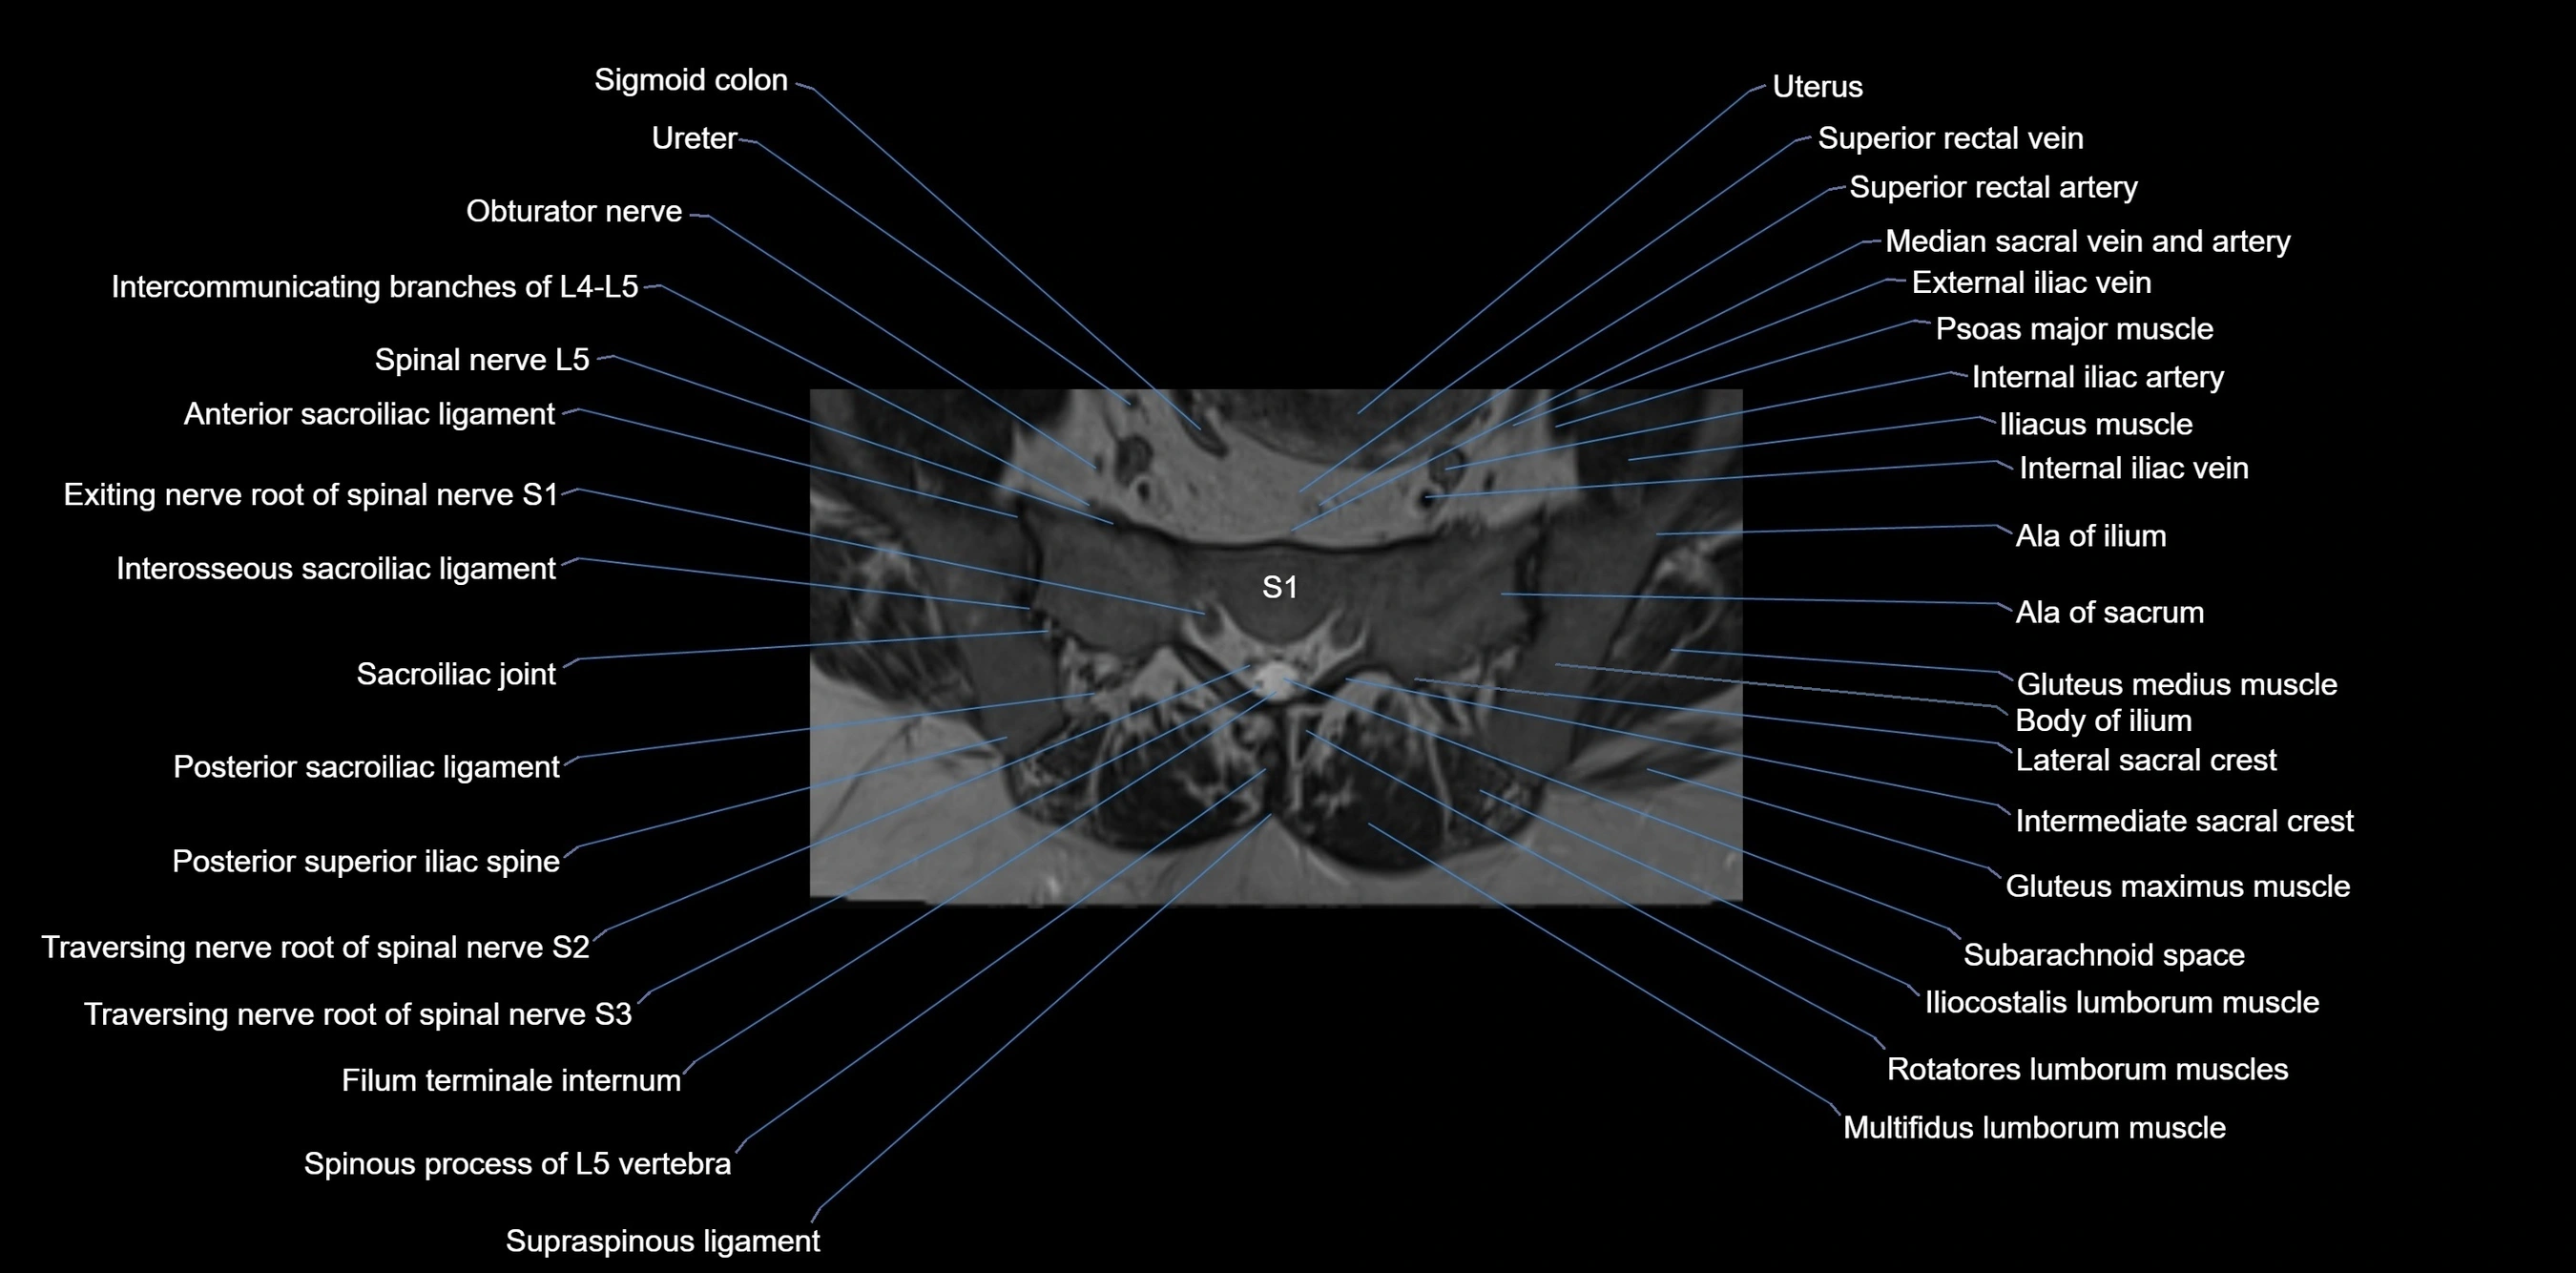

MRI image

image